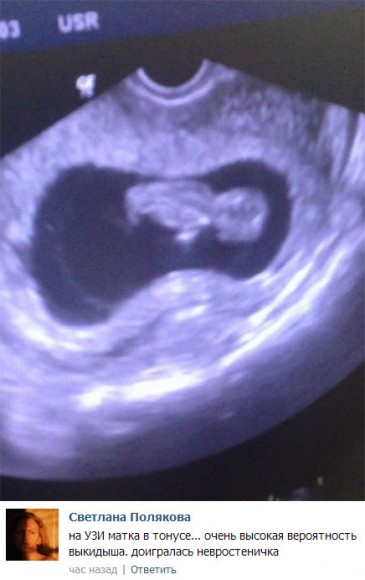

После того, как в эфире показали снимки УЗИ Элины Карякиной, в сети разгорелись бурные дебаты на данную тему. Но, среди обсуждающих данную тему, оказались специалисты в данной области, которые сделали неутешительные выводы по поводу протекания беременности Элины.

Судя по мнению специалиста, беременность Элины под угрозой. Ведь существует огромная угроза выкидыша. Подробности смотрите на скриншоте.